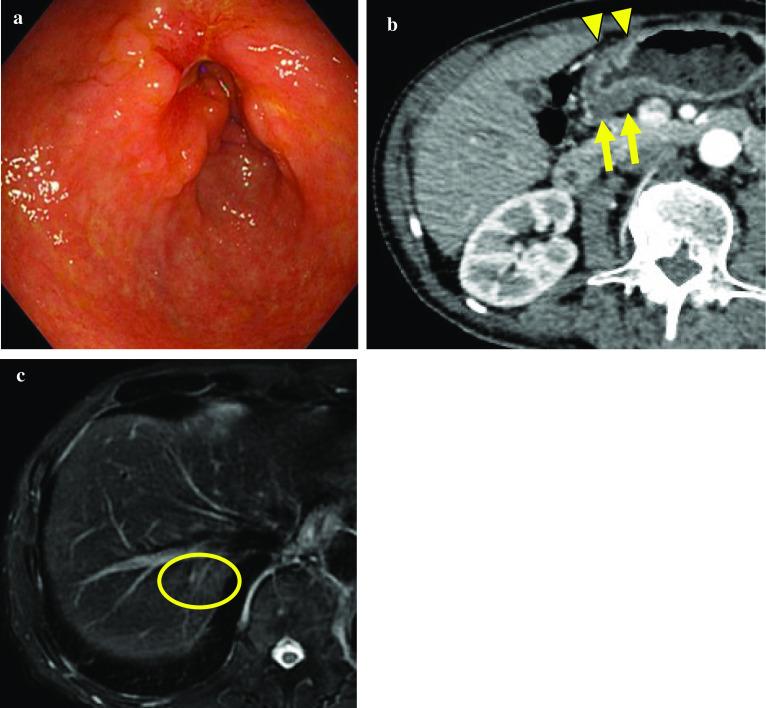

CASE PRESENTATION

A 60-year-old man was diagnosed with type 2 GC with liver metastasis and pyloric stenosis, which was confirmed as the HER2-positive type. He underwent gastrojejunostomy and received capecitabine and cisplatin (XP) + trastuzumab chemotherapy. After three courses of the XP + trastuzumab regimen, shrinkage of the primary lesion and liver metastasis was confirmed and his nutritional parameters markedly improved with a stable oral intake after bypass surgery. He underwent curative R0 resection by distal gastrectomy with D2 lymphadenectomy and partial hepatectomy. Histologically, viable tumor cells were observed in less than one-third of the primary lesion, and only scar tissue without viable cancer cells was noted in the resected liver specimen. His postoperative course was uneventful, and recurrence has not been detected in the 30 months after surgery without adjuvant chemotherapy.

一名60岁男性被诊断为2型胃癌伴肝转移和幽门狭窄,确诊为HER2阳性型。他接受了胃空肠吻合术,并接受了卡培他滨和顺铂(XP)+曲妥珠单抗化疗。在接受三个疗程的XP+曲妥珠单抗治疗方案后,原发灶和肝转移灶缩小得到确认,并且在旁路手术后他的营养参数显著改善,经口摄入量稳定。他接受了远端胃切除术加D2淋巴结清扫和部分肝切除术的根治性R0切除。组织学检查显示,原发灶中存活肿瘤细胞少于三分之一,切除的肝脏标本中仅见无存活癌细胞的瘢痕组织。他术后恢复顺利,在未接受辅助化疗的情况下,术后30个月未检测到复发。